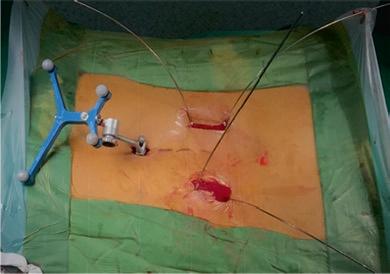

在过去的十年中,TLIF(经椎间孔腰椎椎体间融合)已经成为实现节段性椎体间融合的流行技术。最小通路技术的最新进展有助于通过微创方法进行手术,并提供充分的减压和固体融合。微创技术也有助于避免传统的后路开放入路[1,2]的许多缺点。Schwender等人[3]的一项研究报告了在接受微创TLIF手术的患者的视觉模拟评分和奥斯威特残疾指数评分有临床显著改善,100%的融合率为100%。在MIS病例中,通过更小更窄的解剖进行可视化。退行性脊柱侧弯存在复杂的脊柱病理,如脊柱旋转、透视镜解剖不良、椎弓根不对称和形状异常的椎弓根,可对MIS-TLIF构成严重挑战,导致椎弓根螺钉和钛笼[4]放置不正确。脊柱手术中的图像引导导航对MIS外科医生是一个宝贵的帮助,因为它允许更大的区域。透视可以帮助螺钉放置;然而,它增加了手术时间和辐射暴露给外科医生和手术室人员。据报道,徒手和透视引导下椎弓根螺钉置入时,腰椎移位率高达30%,胸椎移位率高达50%。mal定位的螺钉可能对脊髓、神经根和大血管造成潜在的损伤,也会降低脱位的稳定性。医学法律上对患者安全的担忧进一步加强了图像引导螺钉放置的必要性,以提高[5]的准确性。

计算机辅助脊柱手术(CASS)是一门使用新的基于计算机的技术的学科,包括立体定向、导航手术和机器人技术。导航辅助脊柱手术是一组技术,它允许外科医生在手术中获取与手术器械相关的实时、三维和虚拟的脊柱图像。